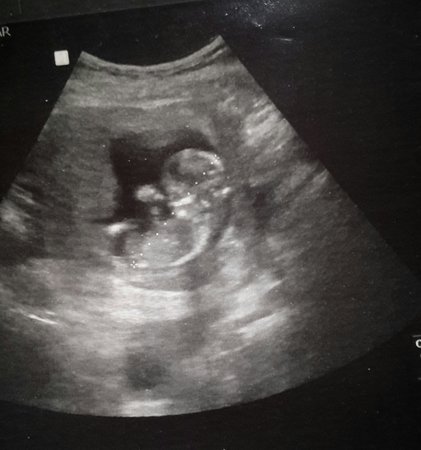

First time poster here! Can anyone please take a guess on baby's gender based on skull or nub (not sure the nub is visible?). All guesses welcome!

Maybe girl from 3rd pic but quality is really bad! What's baby gestation? That can change things!